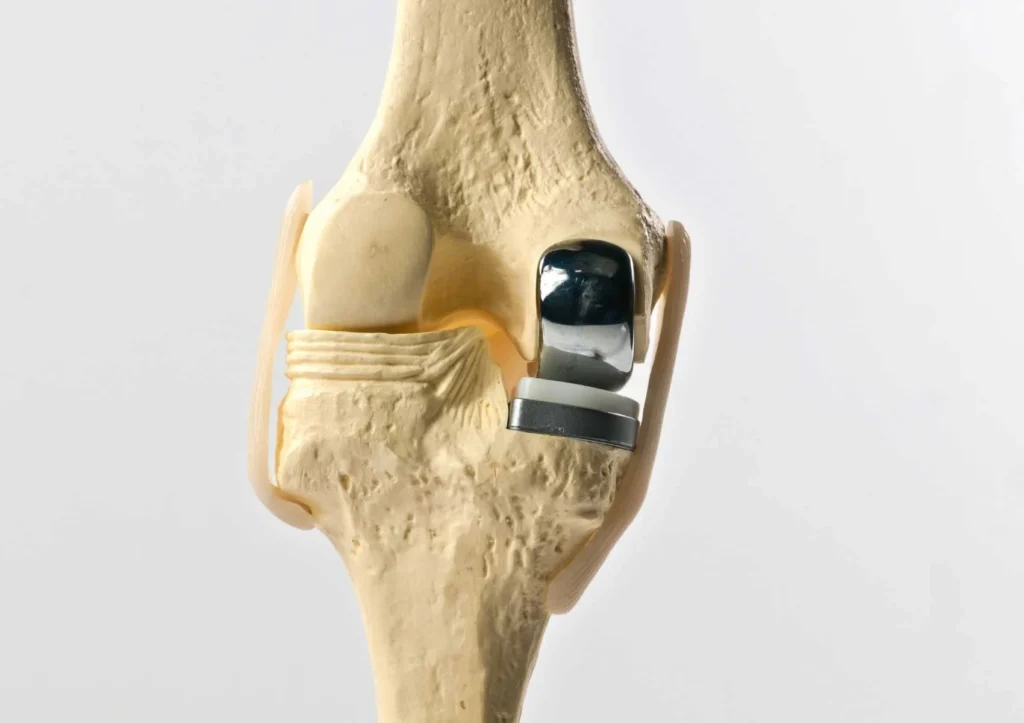

Diz eklemi üç kompartmandan oluşmaktadır. Eğer bu kompartmanlardan ikisinde artrit bulguları var ise bu durumda total diz protezi uygulanmalıdır.Eğer artrit yalnızca bir kompartmanda sınırlı ise minimal invazif kısmi diz protezi (unikompartmantal diz protezi) tercih edilmelidir.

Yıpranmış olan eklemin her iki yüzünün, metal ve polietilenden yapılan, ağrısız şekilde eklem hareketine izin verecek şekilde özel parçalar ile kaplanarak yapay bir eklem meydana getirilmesidir.

Eklemi meydana getiren üç kemiğin (femur, tibia ve patella) birbirleriyle temas halinde olan yüzlerindeki aşınmaya uğramış kıkırdak dokusu, kemik tabakası ile birlikte kesilerek çıkarılır, ardından ölçü ile belirlenen uygun boyutlardaki protez parçaları, dolgu maddesi olarak kullanılan ve polimetil metakrilat olarak adlandırılan kemik çimentosu ile hazırlanmış kemik yüzeylere tutturulur. Bu yöntemle eklem yüzleri, metal ve plastikten yapılmış parçalarla yeniden kaplanmış olur.

Kısmi bir dizin avantajı, hasarsız olan kıkırdağı muhafaza ederken dizin yalnızca hasarlı kıkırdağını kaplar. Bu prosedürün faydaları daha küçük bir yara, daha hızlı bir iyileşme ve daha az kemik çıkarılmasını kapsar.

Yarım protez eklemin sadece hasta olan bölümünü tedavi eder. Böylece sağlıklı kısım feda edilmemiş olur. Bu yüzden bu ameliyat diğer proteze göre daha erken yapılabilir ve hastaya rahatlık sağlar.

Total diz protezi ile karşılaştırıldığında, avantajları arasında yüksek oranda hasta tatmini, daha kısa operasyon süresi, hastanede daha kısa yatış süresi, minimal olarak kabul edilebilecek kan kaybı, daha az enfeksiyon oranına sahip olması, diz kinematiğini çok daha normale yakın oranda sağlaması, ameliyat sonrası iyileşmeyi daha erken sağlaması, daha iyi hareket açıklığı sağlaması bulunmaktadır.